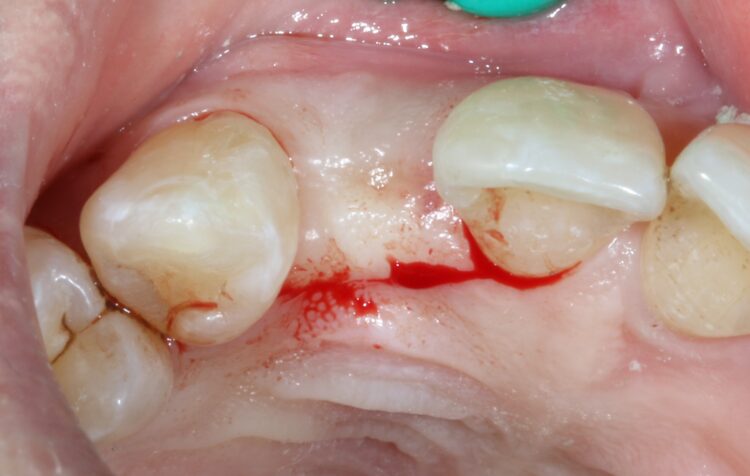

The provisional stages

Three months later a small crestal incision was performed to expose and remove the healing cap and impressions taken to construct an under-contoured screw-retained provisional crown. Over a period of two visits, composite was incrementally added to the subgingival portion of the temporary crown to expand and modify the soft tissue emergence profile until an acceptable shape was achieved.

A new impression was taken capturing the NEW transmucosal shape and a customised abutment and zirconia crown were fabricated as a one-piece screw-retained restoration and fitted to complete the case.